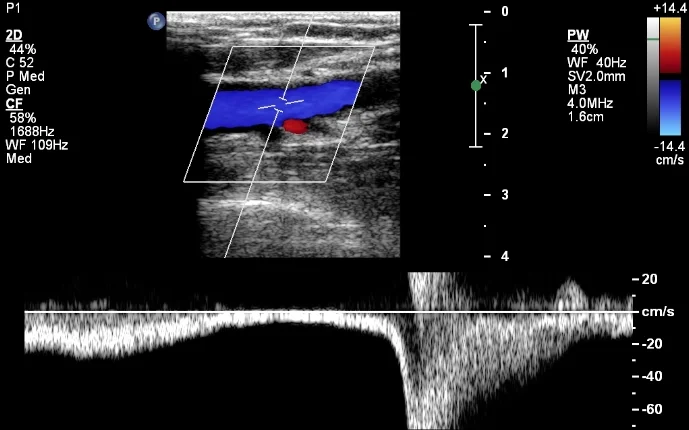

<p>what is being shown in this image?</p>

what is being shown in this image?

venous reflux